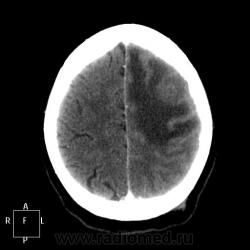

КТ. Мужчина 33 лет. Поступал с подозрением на инсульт.

Болен в течение 3-х месяцев, постепенно нарастала клиника; лечился 2 недели у невролога амбулаторно с вялым гемипарезом. Привезен по "скорой помощи" с диагнозом при поступлении: ишемический инсульт в бассейне левой СМА. Предполагаю глиобластому. Прошу высказать коллег свое мнение!

Согласен с Вами на счет глиобластомы,однако нельзя забывать и о возможности солитарного МТС.Абсцесс можно исключить,учитывая тот факт,что околоносовые пазухи воздушны.

На метастаз очень похоже. Да и болеет всего 3 месяца.

А что, абсцесс мозга имеет исключительно риногенное происхождение?

Я бы сказал, что это образование как раз больше похоже на абсцесс, чем на опухоль.

Я в МРТ новичок. Так что мое мнение можно и не учитывать. Но теоритечески знаю, что если сделать DWI и карту диффузии, то абсцесс от опухоли можно отличить. Может Евгений нам что-то подскажет? На абсцесс конечно похоже: тонкие, ровные стенки, но на одной из них какое-то утолщение - мягкотканный компонент, как мне кажется.

Там два узелка, копящие контраст. Именно поэтому остановилась на глиобластоме. Клиника противоречит классической картине абсцесса. Взяла у жены пациента телефон, надеюсь, что дальнейшую судьбу удастся проследить.

Забыла про этот случай, а тут нейрохирург напомнил. С моим заключением "глиобластома", пациент был направлен в онкоцентр, где выполнена МРТ с заключением "объёмное образование головного мозга"...

Интересное в другом: пациенту через какое-то время сделан анализ крови на ВИЧ, который оказался положительным. Были пересмотрены все данные и назначено пробное лечение против токсоплазмоза, которое дало выраженную положительную клиническую динамику. Не оперировался. На контроль пациент ко мне не поступал, всё со слов нейрохирурга, но история показалась очень интересной).

Думаю, что тогда вполне могла и ошибиться. Пациента и контроля не видела, но если самочувствие лучше на фоне специфической терапии, то волей-неволей признаешь возможность токсоплазмоза.

Молодой мужчина. Неправльной формы с неровынми контурами тонкостенное образование. Очень важный признак - небольшой узелок пристеночно. Все эти признаки могут навести на мысль что тут возможен ВИЧ и токсоплазмоз. Пробное лечение - если возникают характерные кровоизлияния в полости - показатель того что это именно токсоплазмоз (положительная динамика от лечения).